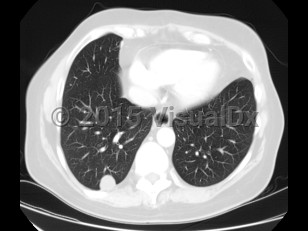

The second most common presentation is pulmonary nodules. Patients are usually asymptomatic but may present with cough, hemoptysis, fever, and chest pain. Most frequently, however, infection in these patients presents as a solitary nodule on chest radiographs, and the diagnosis is usually made on pathology (done to rule out other serious conditions; see Differential Diagnosis & Pitfalls). Dirofilaria immitis is the most common cause of pulmonary lesions, although D. repens has also been reported.